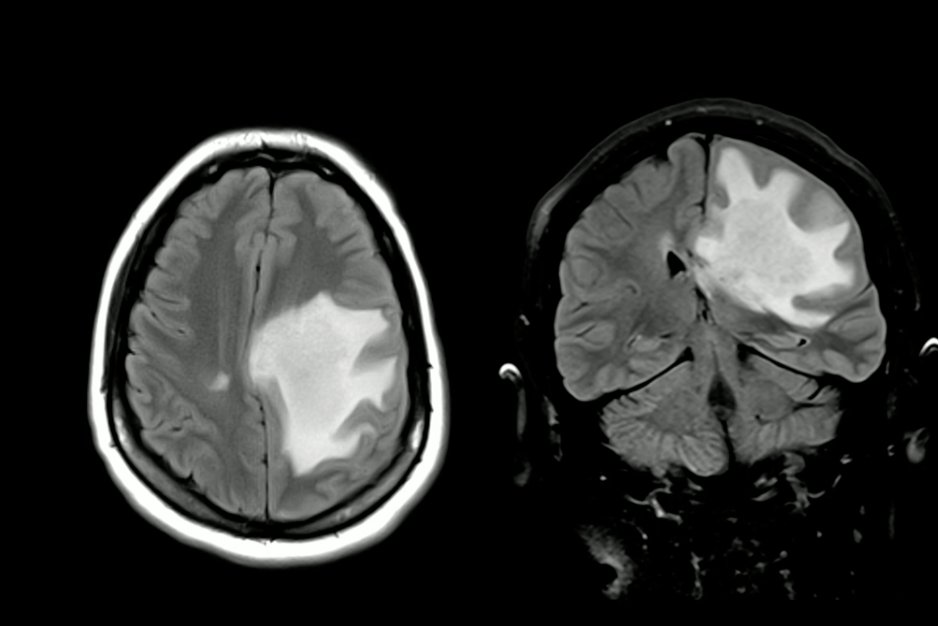

This is not GBM.... what is it, #NeuroTwitter?? the key -- pull your eyes away from the most exciting part of the brain (in this case the left) and look at the whole picture. From #JoshKlein's lecture @ #AANSC @aanmember